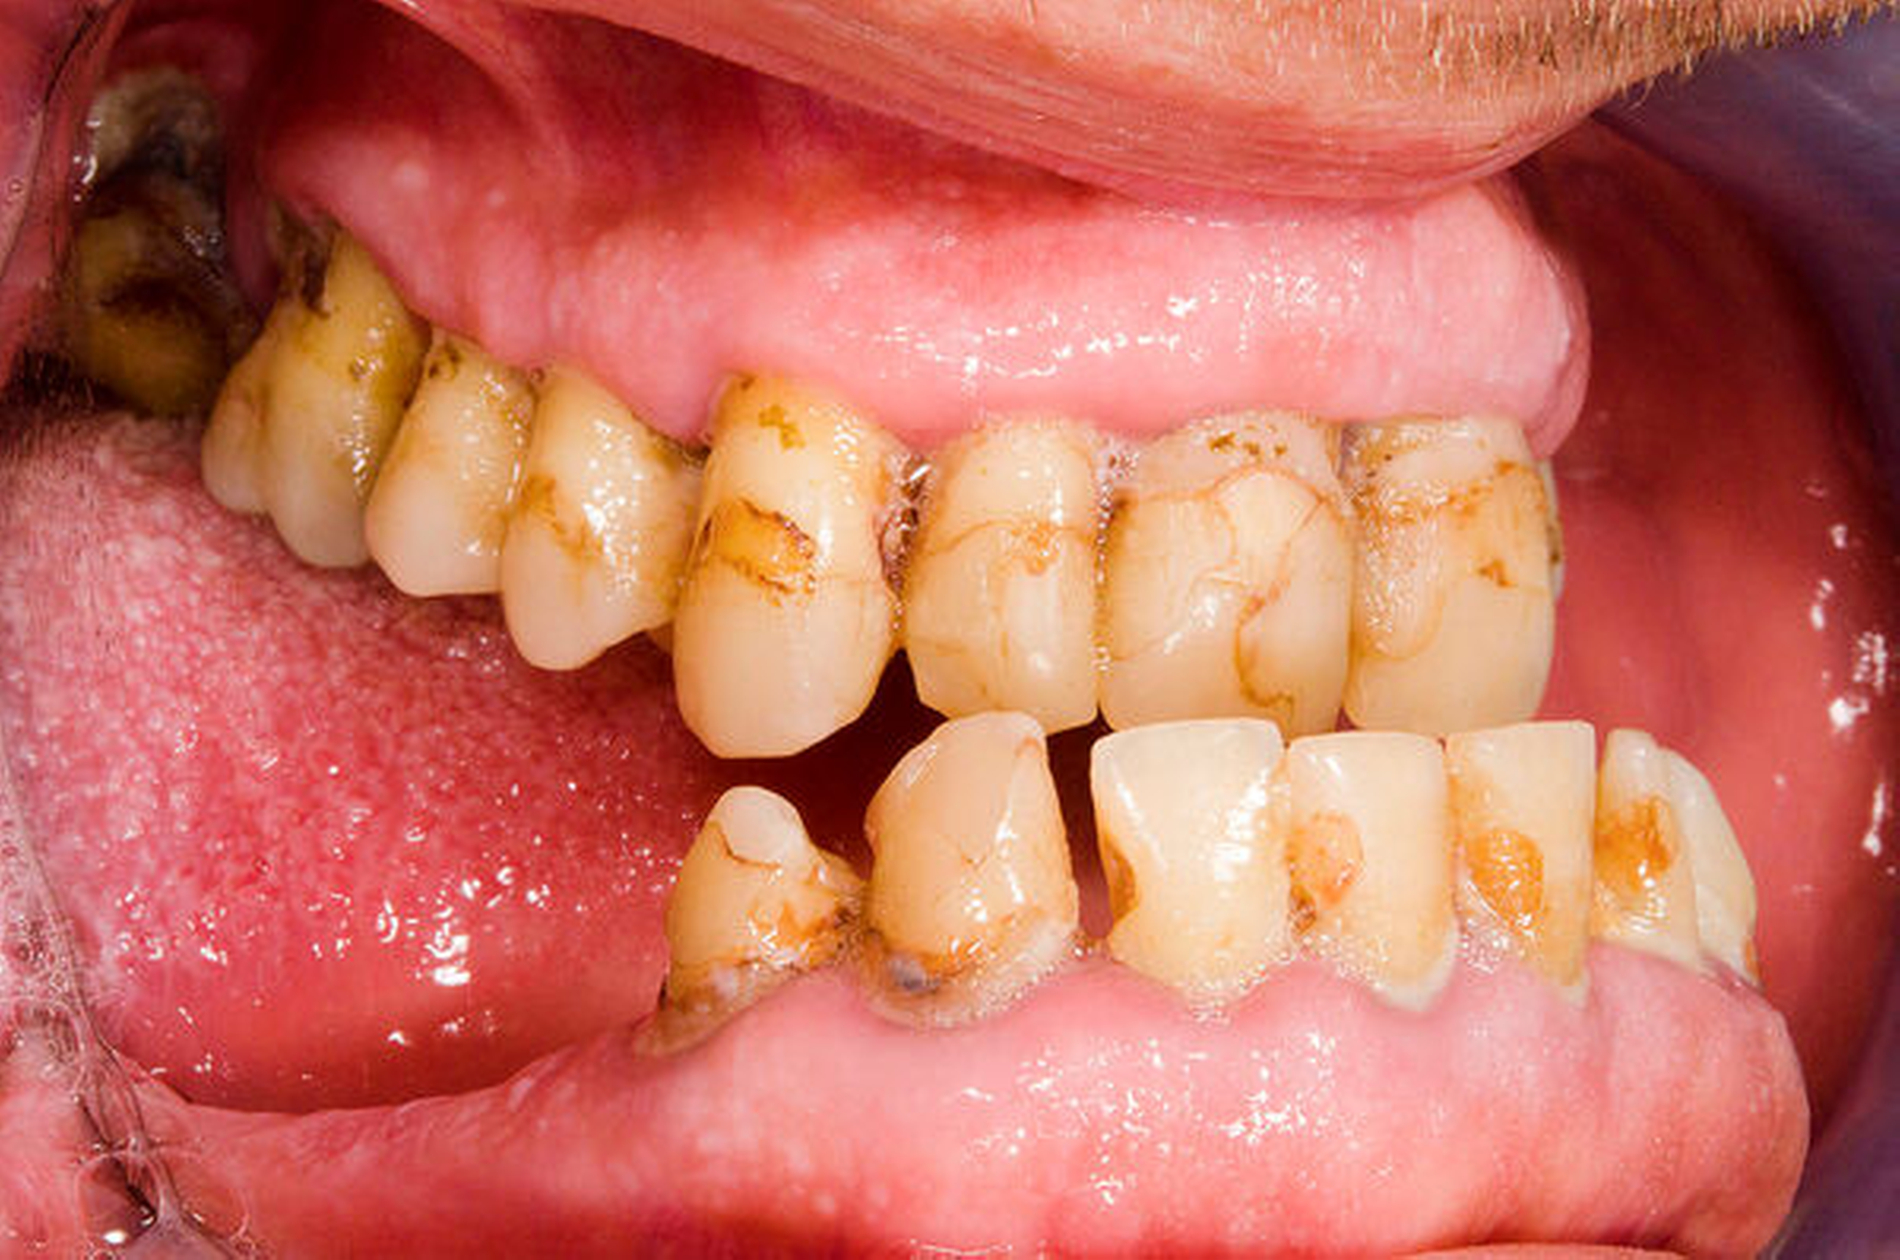

Der 39-jährige Patient (Abbildungen 1 und 2) suchte 2015 aufgrund einer zunehmenden Okklusionsstörung seinen Hauszahnarzt auf. Diesem fiel die ausgeprägte mandibuläre Hyperplasie auf und er überwies den Patienten zur endokrinologischen Diagnostik aufgrund des Verdachts auf eine Akromegalie. Im Rahmen der Anamnese äußerte der Patient zudem, dass er bereits vor einem Jahr eine Vergrößerung seiner Finger bemerkt habe.

Bei der ersten Vorstellung in der Dysgnathie-Sprechstunde imponierte eine 10 mm große, umgekehrte, sagittale Frontzahnstufe. Die Mittellinie des Unterkiefers wich um 4 mm nach rechts ab. Die Zähne des teilbezahnten Ober- und Unterkiefers hatten jeglichen Kontakt verloren (Abbildungen 5 und 7).

Die unverhältnismäßig große Zunge zeigte dentale Impressionen. Nach Festlegung des Zielbisses in Abstimmung mit den Kollegen der Prothetik erfolgte eine bimaxilläre Umstellungsosteotomie mit Vorverlagerung des Oberkiefers um 8 mm nach LeFort-I-Osteotomie und Rückverlagerung des Unterkiefers nach sagittaler retromolarer Osteotomie (Abbildungen 6 und 8). Im gleichen Zug wurde eine Zungenreduktionsplastik nach Rheinwald [Egyedi et al., 1964] durchgeführt.